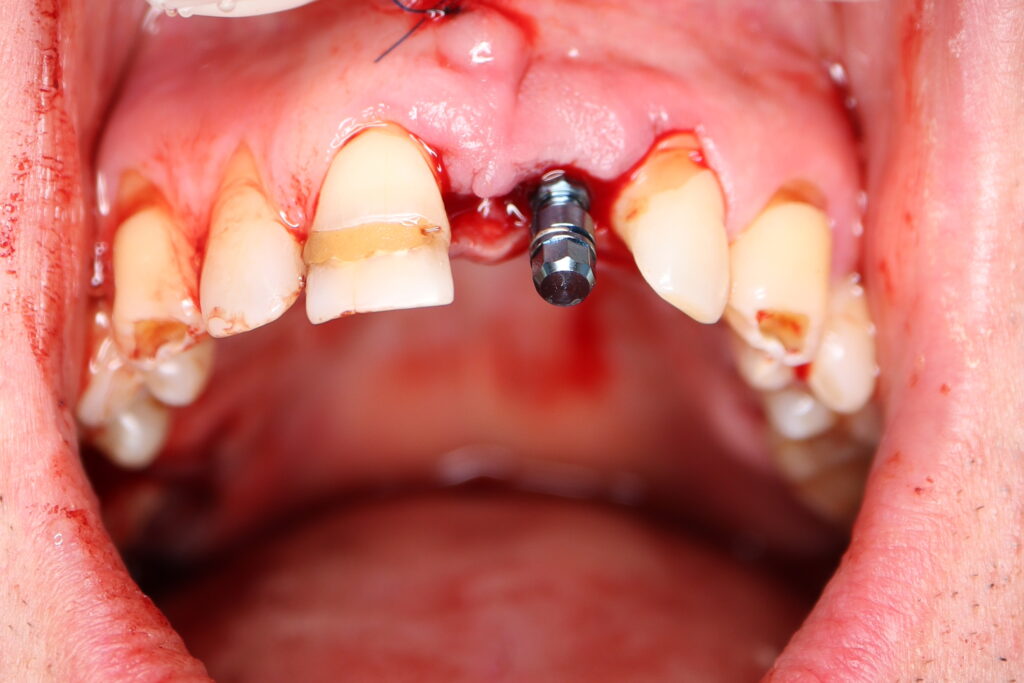

Процесс работы

Что было сделано:

Лечение состояло из двух этапов: хирургический и ортопедический. Длилось 4 месяца.

Были установлены 4 имплантата Straumann BLT. На верхней челюсти в области зуба 2.1 в одно посещение был установлен имплантат и изготовлена временная коронка.

Также в данной области выполнена пластика десны.

хирургический этап

Это фото может содержать тяжелый для восприятия контент